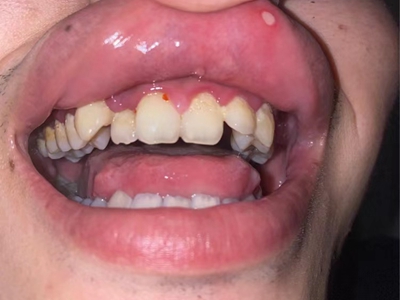

慢性龈炎又称边缘性龈炎或单纯性龈炎,主要表现为游离龈和龈乳头因炎性水肿,而变为鲜红或暗红色,龈缘变厚,龈乳头圆钝肥大。慢性龈炎的患病率高,治愈后仍可复发,部分患者可发展成为牙周炎。

慢性龈炎的病损部位一般局限于游离龈和龈乳头,以前牙区为主,尤其以下前牙区最为显著,患者常因刷牙或咬硬物时牙龈出血而就诊。游离龈和龈乳头颜色变为鲜红或暗红色,病变较重时炎性充血可波及附着龈。龈缘变厚,龈乳头圆钝肥大,可增生呈球状,覆盖牙面。牙龈松软脆弱,缺乏弹性。